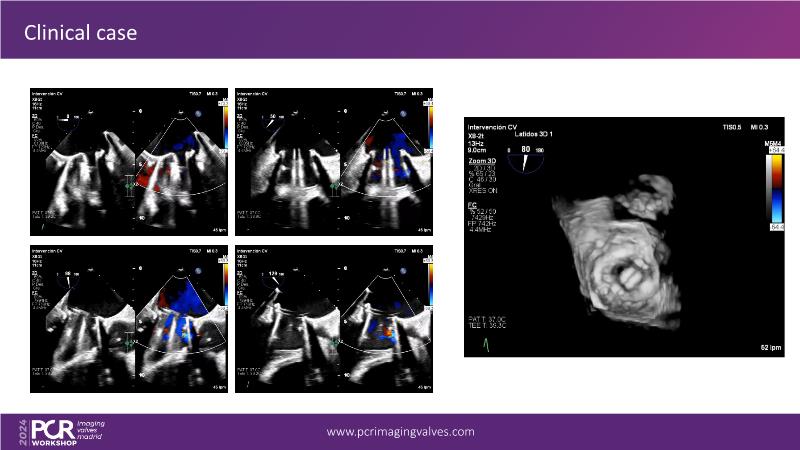

Explore cutting-edge transcatheter valve interventions for mitral and aortic valve disorders, including valve-in-valve procedures and management strategies for paravalvular leakages, and learn about diagnosing and treating mitral annular calcification and transcatheter options in infective endocarditis.

- To get tips and tricks for guidance of transcatheter intervention